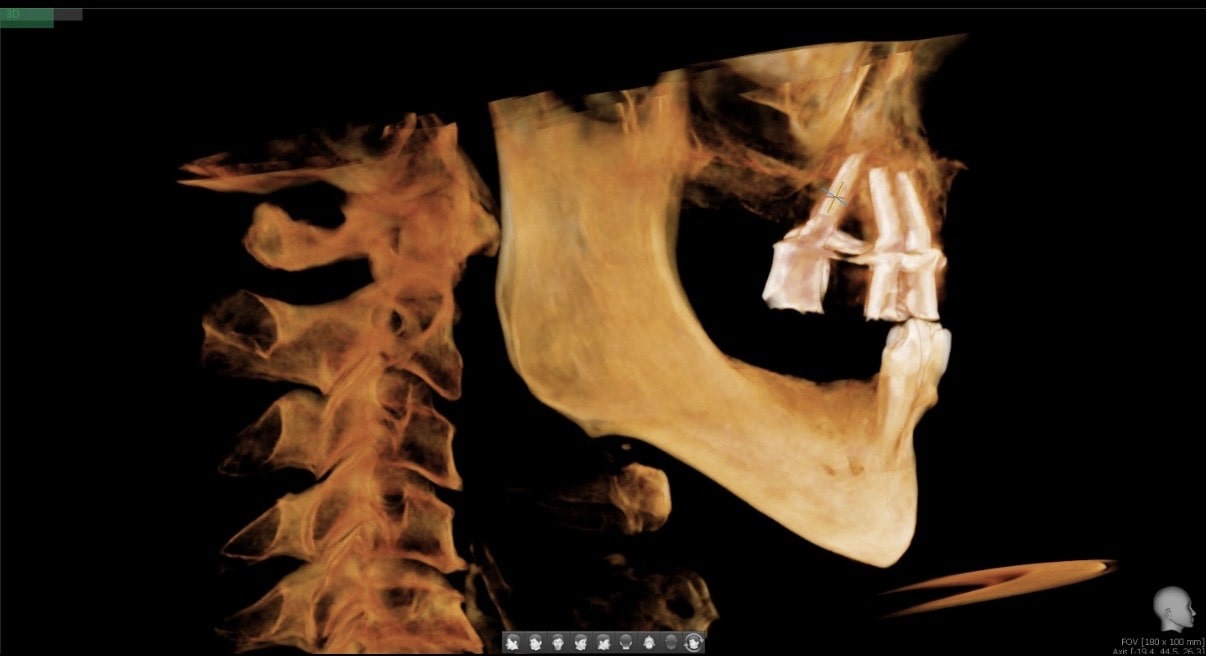

We knew that John was a good candidate for All-on-4 implants, so our team worked to design a bright, healthy smile for John. During our comprehensive examination, we took x-rays, surveyed the damage, and created an upper arch that restored the natural appearance of his teeth.